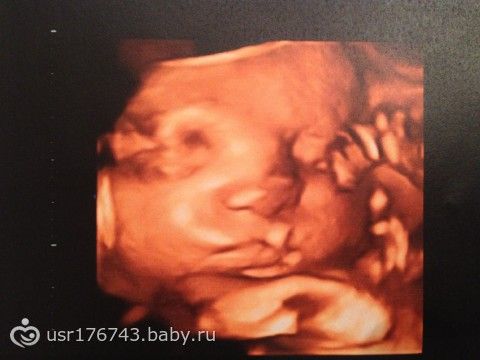

На прошлой неделе ходили на узи, наш любимый мужчина Михаил весит 1545 г, рост — 39 см, лежит головкой правильно вниз, и толкает мамку в правое ребро стопочками длинной 6 см!

(фоточки маси прилагаются).

У нас всё хорошо, никаких обвитий, и допплер тоже отличный, чему мы очень рады.